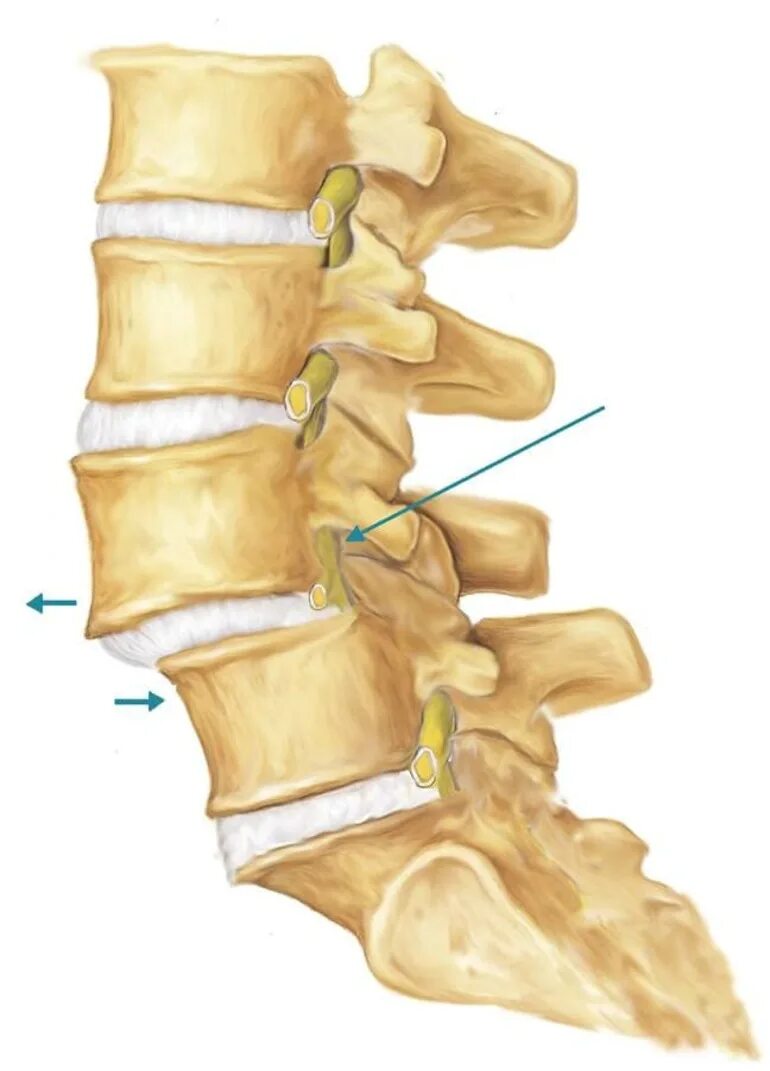

Спондилоартроз протрузии дисков спондилез